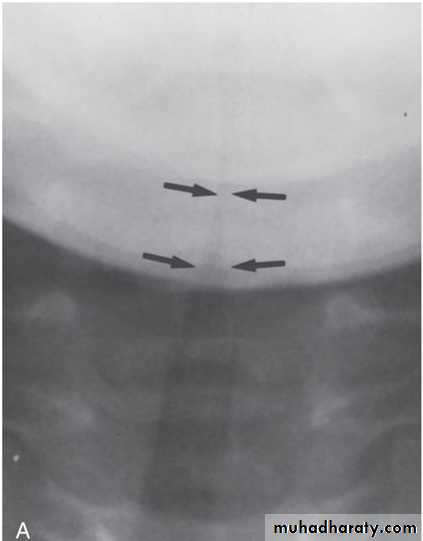

Croup (Laryngotracheobronchitis)• Croup, or laryngotracheobronchitis, is the most commoninfection of the middle respiratory tract.• The most common causes of croup are parainfluenza viruses(types 1, 2, and 3) and respiratory syncytial virus.• Croup is most common in children 6 months to 3 years of age,with a peak in fall and early winter. It typically follows acommon cold.CLINICAL MANIFESTATIONS• The manifestations of croup are a harsh barking cough,hoarseness, inspiratory stridor, low-grade fever, andrespiratory distress that may develop slowly or quickly.• Signs of upper airway obstruction, such as labored breathingand marked suprasternal, intercostal, and subcostalretractions, may be evident on examination.• Wheezing may be present if there is associated lower airwayinvolvement.LABORATORY AND IMAGING STUDIES• Anteroposterior radiographs of the neck show thediagnostic subglottic narrowing of croup known asthe steeple sign.• Many rapid tests (PCR or antigen) are available forparainfluenza viruses and RSV.PA view of the upper airway shows the so-called steeple sign, thetapered narrowing of the immediate subglottic airway (arrows)